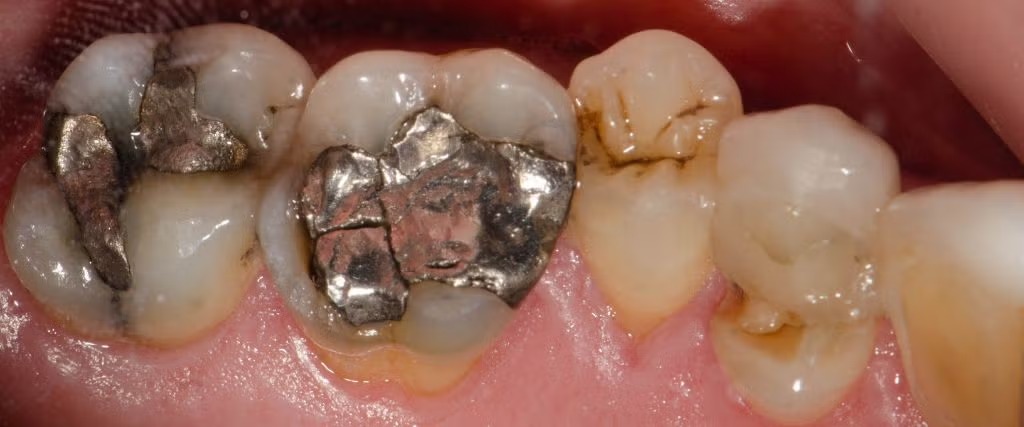

The dental industry has undergone a significant transformation over the past two decades. Once considered the gold standard for dental restorations, mercury amalgam fillings have